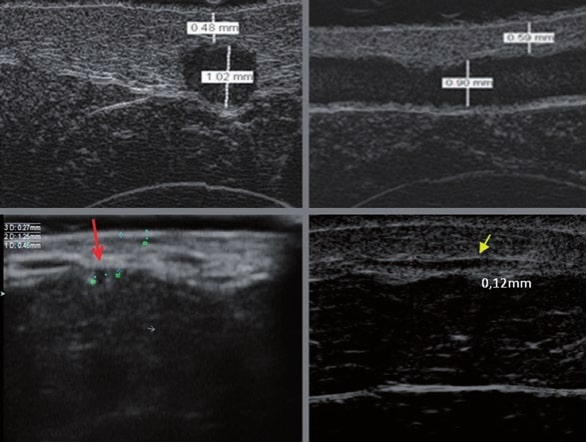

La sonographie Doppler permet l’imagerie des gros vaisseaux et des perforantes qui sont généralement situés dans les couches plus profondes du tissu sous-cutané (fig. 1). Malheureusement, la sonographie conventionnelle n’est pas capable d’imager les vaisseaux plus petits. Afin de visualiser les vaisseaux plus petits situés près de la surface de l’épiderme et dans la couche supérieure du tissu sous-cutané, l’EHF est utilisée (fig. 1). Grâce à l’utilisation de transducteurs dont les fréquences sont supérieures à 20 MHz, une image échographique à haute résolution est obtenue dans laquelle nous pouvons différencier des structures qui sont plus petites que 0,1 mm. Cependant, plus la résolution est élevée, moins la pénétration du faisceau ultrasonore dans les couches de la peau est profonde. Par conséquent, selon le transducteur et l’appareil, il est possible de pénétrer la peau jusqu’à une profondeur maximale de 20–30 mm. Une telle pénétration, associée à une haute résolution d’image, permet l’évaluation de vaisseaux sanguins même très petits (fig. 2). Pendant l’examen avec l’utilisation de transducteurs à haute fréquence, on peut évaluer avec précision le trajet et l’emplacement des petits vaisseaux dans la peau. Cela est particulièrement pertinent pour la sélection de la méthode de fermeture des vaisseaux et la planification de la procédure, car en pratique, la surface de la peau ne montre très souvent qu’un petit nombre de vaisseaux ou un léger fragment de vaisseau – ce n’est qu’après l’examen US que nous pouvons déterminer leur nombre réel et leur trajet. Pour une fermeture efficace du vaisseau, il est nécessaire de le faire sur toute sa longueur. Elle ne doit pas se limiter au fragment vu « à l’œil nu » à la surface de la peau, car la fermeture du fragment entraînera sa recanalisation rapide(7). Fréquemment, le vaisseau visible à la surface de la peau change de trajet, devient plus tortueux et se déplace vers les couches plus profondes de la peau(8). Par conséquent, le trajet de la veine et des perforantes doit être bien connu et déterminé avant la procédure. L’EHF permet également l’imagerie des perforantes entre les petits vaisseaux. De plus, outre l’évaluation du trajet et de l’anatomie, l’image échographique, grâce au logiciel d’échographie, permet également de déterminer les paramètres de base tels que le diamètre du vaisseau, l’épaisseur de sa paroi, la profondeur dans la peau ainsi que la présence ou l’absence de perfusion à l’intérieur du vaisseau(6) (fig. 3). Grâce au transducteur électronique multi-éléments d’une fréquence de 40 MHz introduit sur le marché par Ultrasonix, il est également possible de visualiser la perfusion des vaisseaux en mode Doppler couleur (fig. 4).